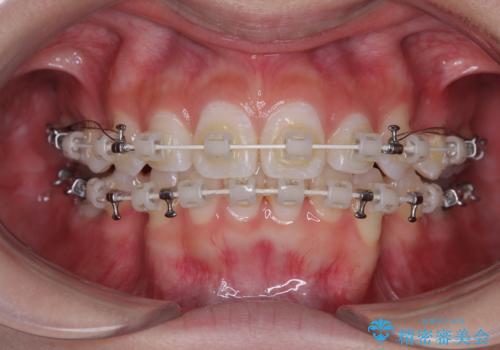

- 矯正装置

- 審美装置

- 2年

- 10-30回